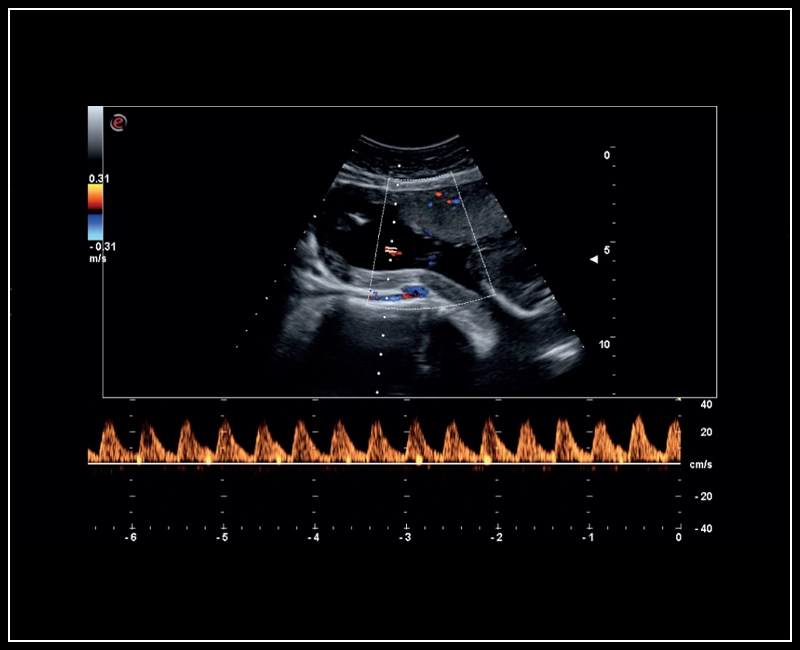

MyLab™Sigma - Umbelical cord PW Doppler mode

MyLab™Sigma - Umbelical cord PW Doppler mode